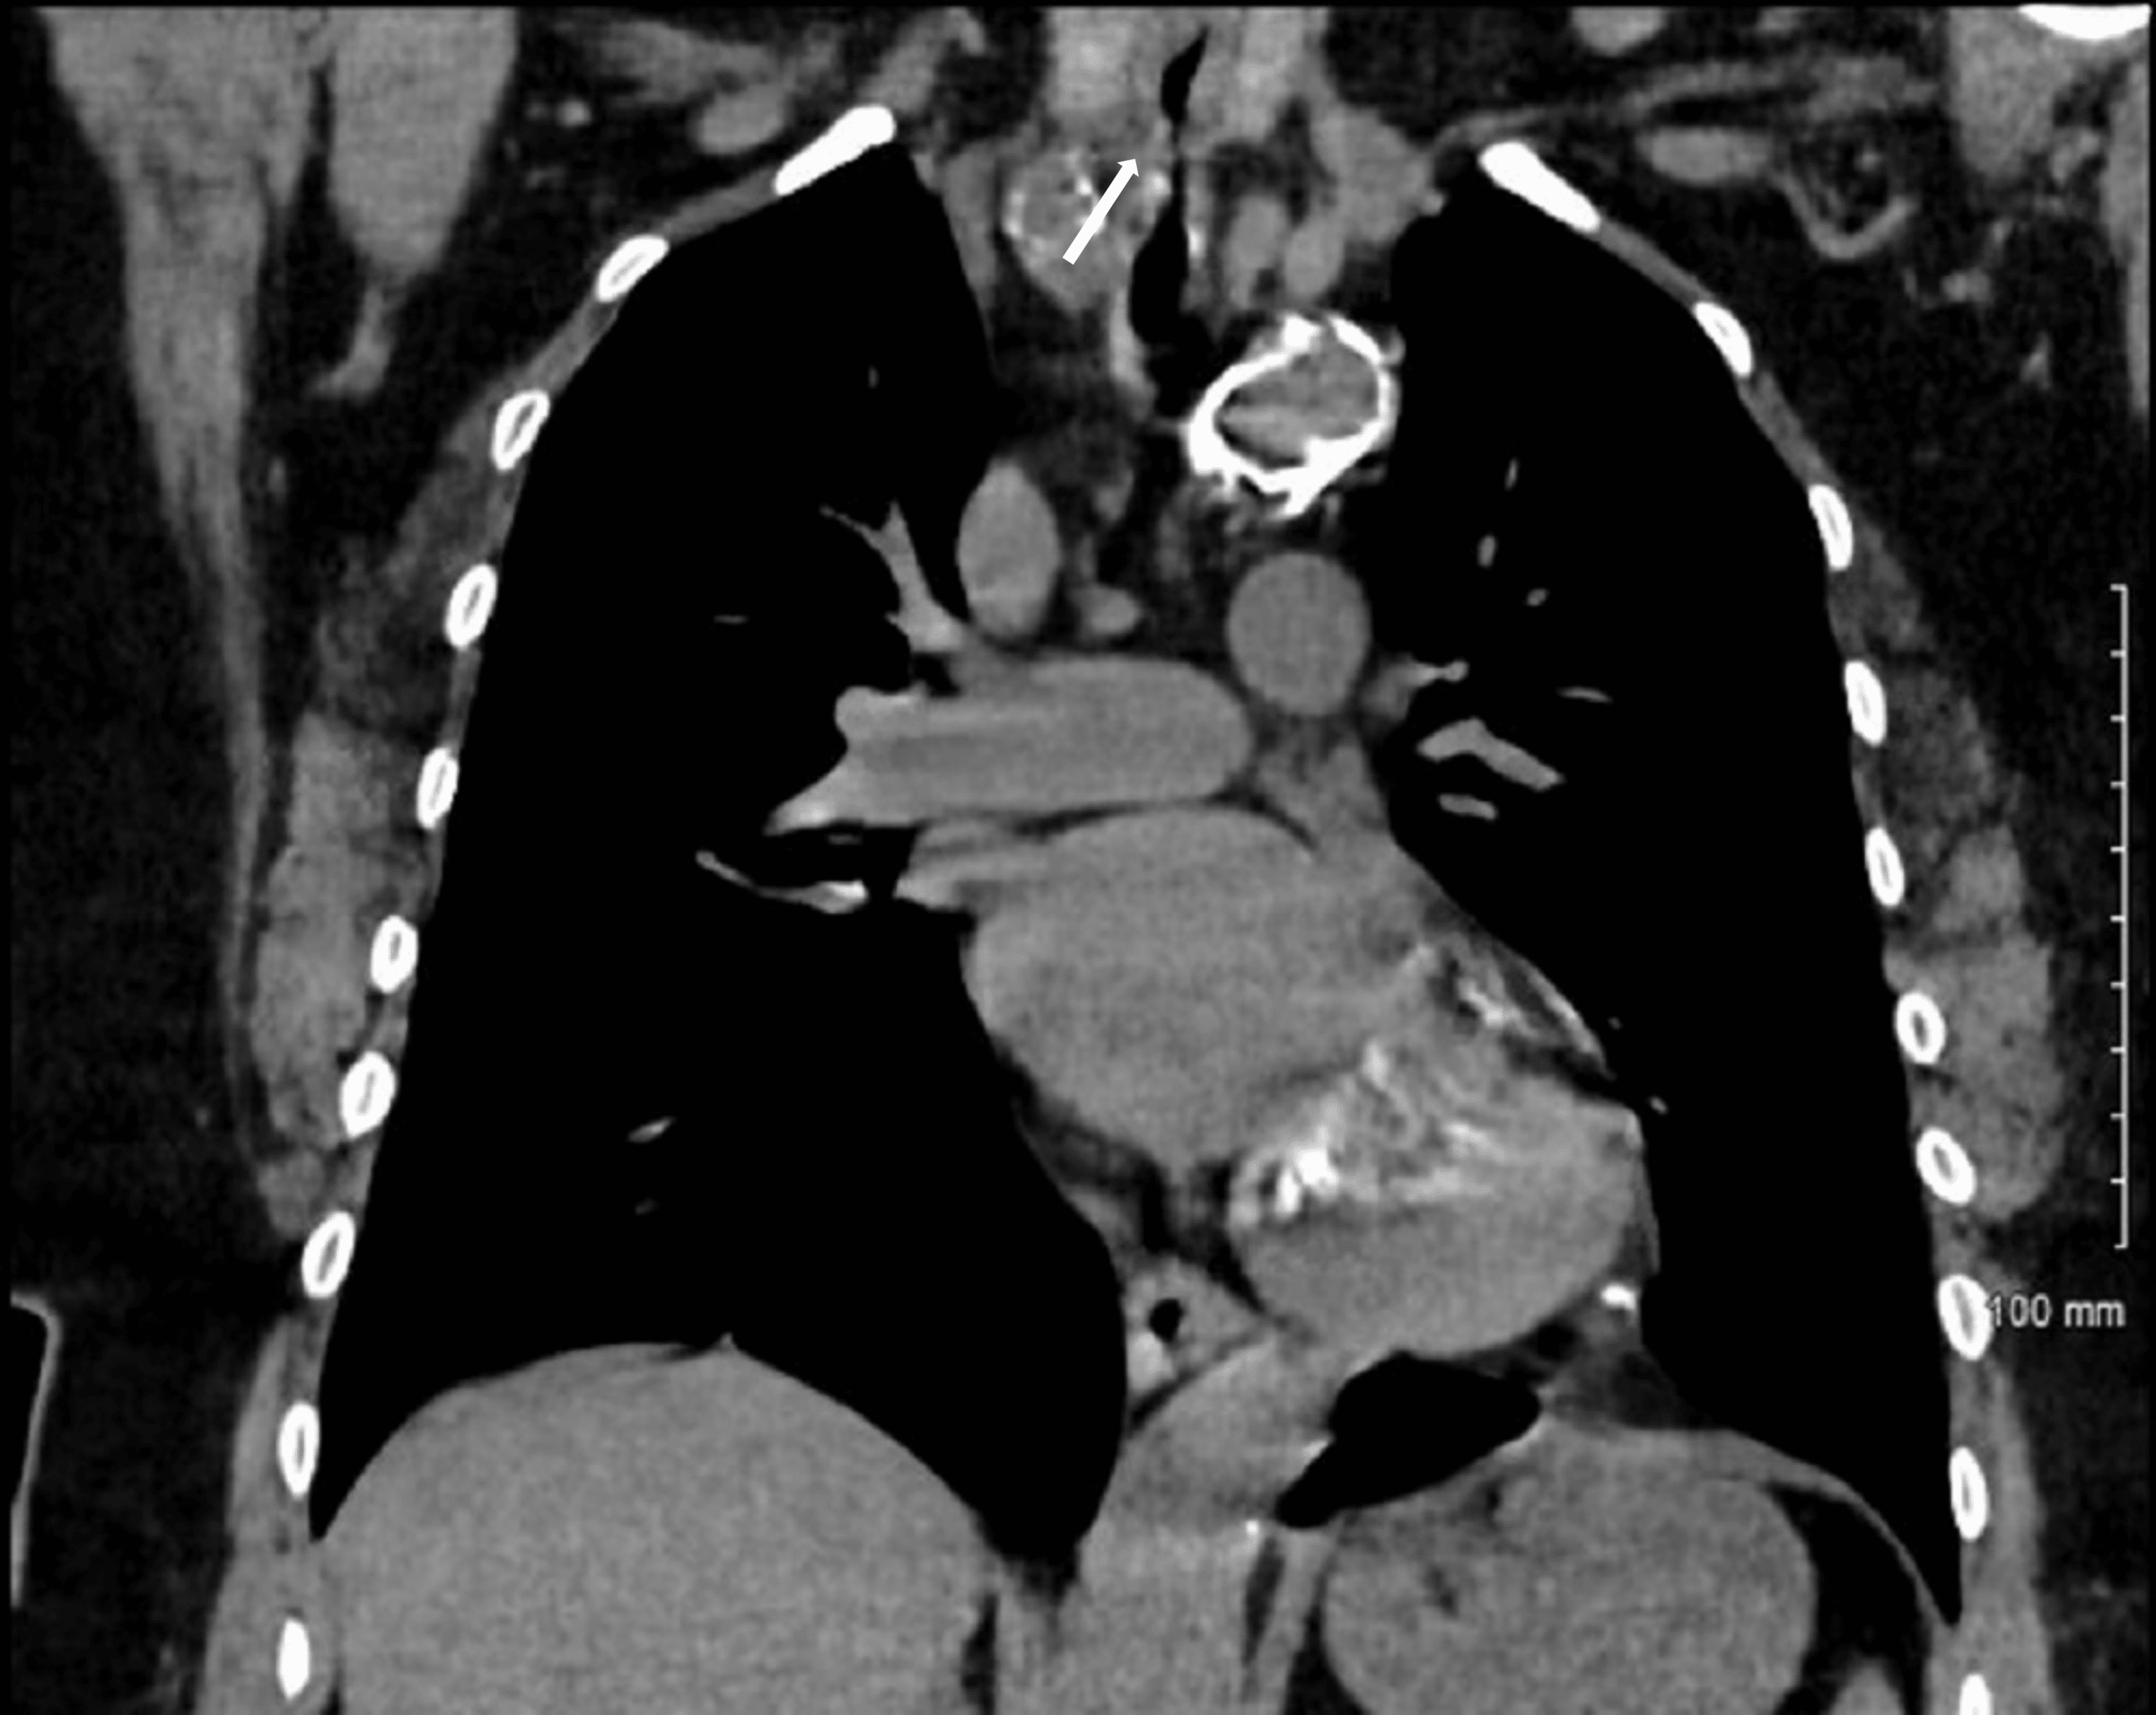

From www.cureus.com

Cureus AngiotensinConverting Enzyme InhibitorInduced Angioedema Tracheal Stenosis Following Endotracheal Intubation It can also arise as part of the spectrum of. Tracheal stenosis can present following intubation and tracheostomy. Tracheal stenosis is a common complication of endotracheal intubation or tracheostomy, resulting in significant morbidity. The most common procedure to correct postintubation tracheal stenosis was tracheal resection with an anastomosis between trachea. Nonmalignant tracheal stenosis is a potentially life threatening conditions that. Tracheal Stenosis Following Endotracheal Intubation.